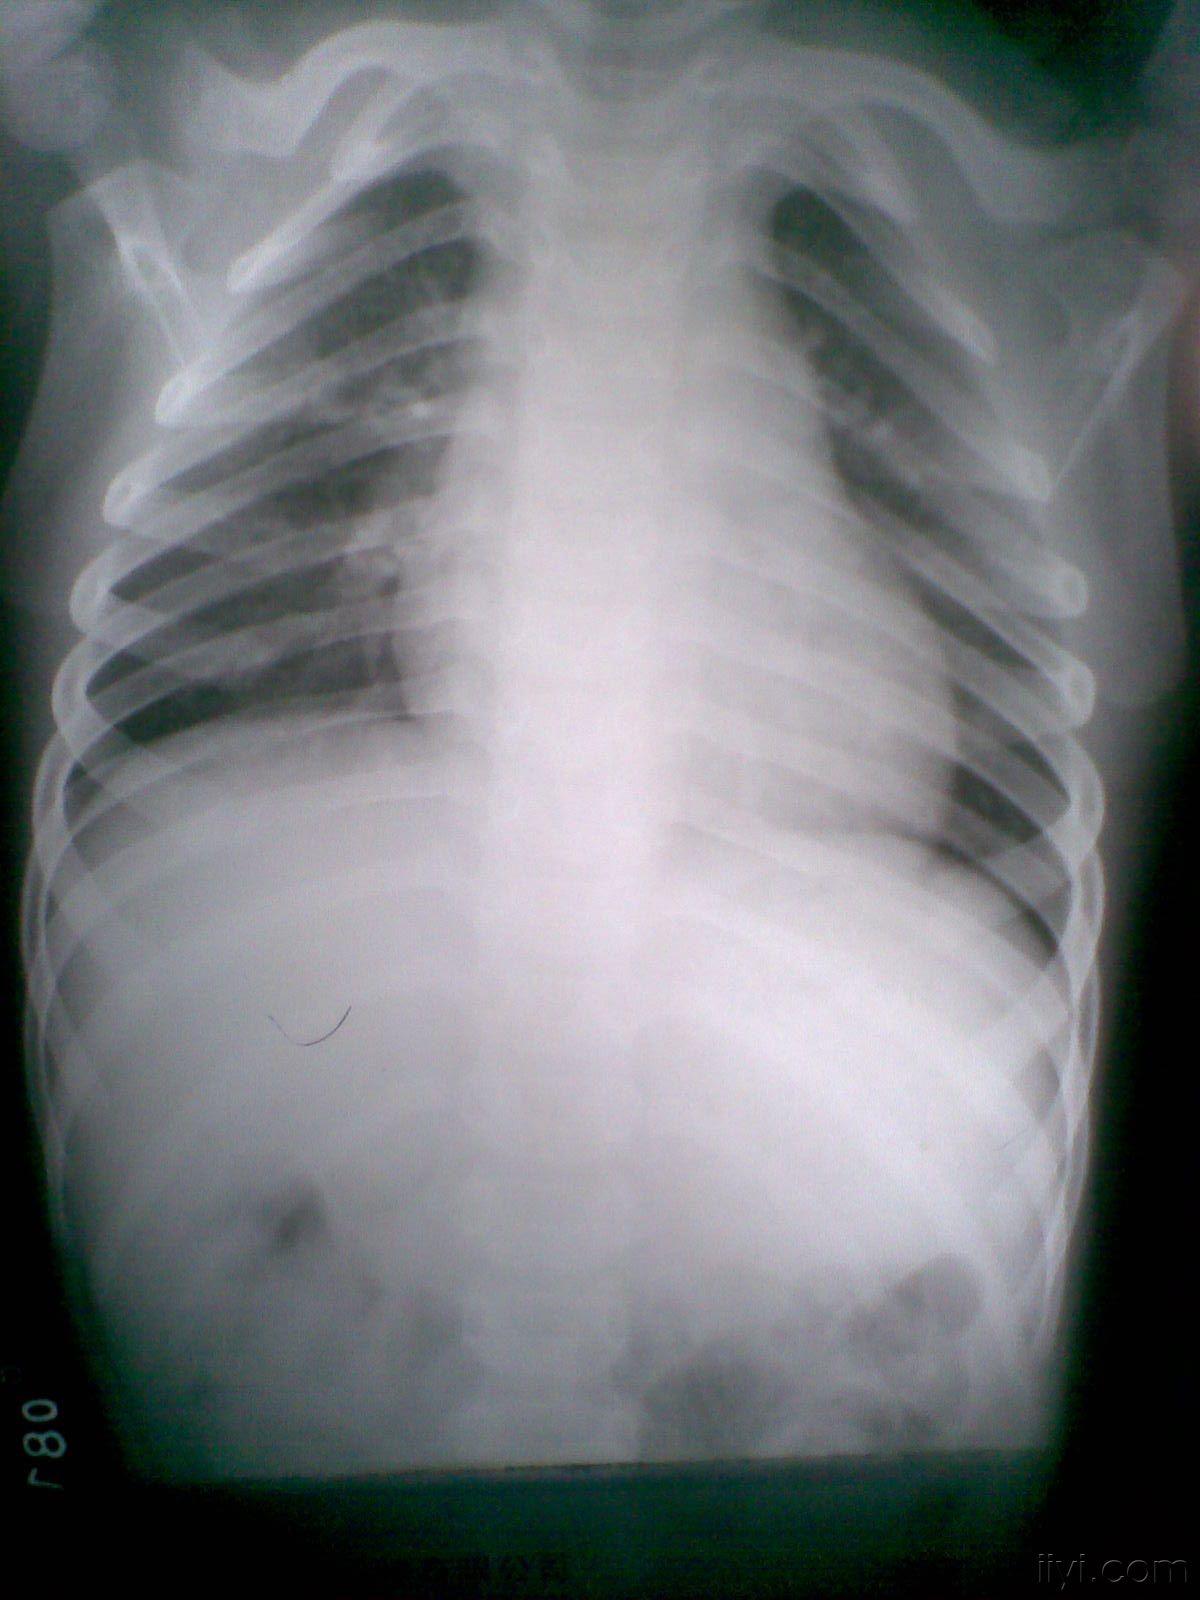

图一 镜面右位心 心尖和胃泡位于右侧

胸片展示胃泡特别大